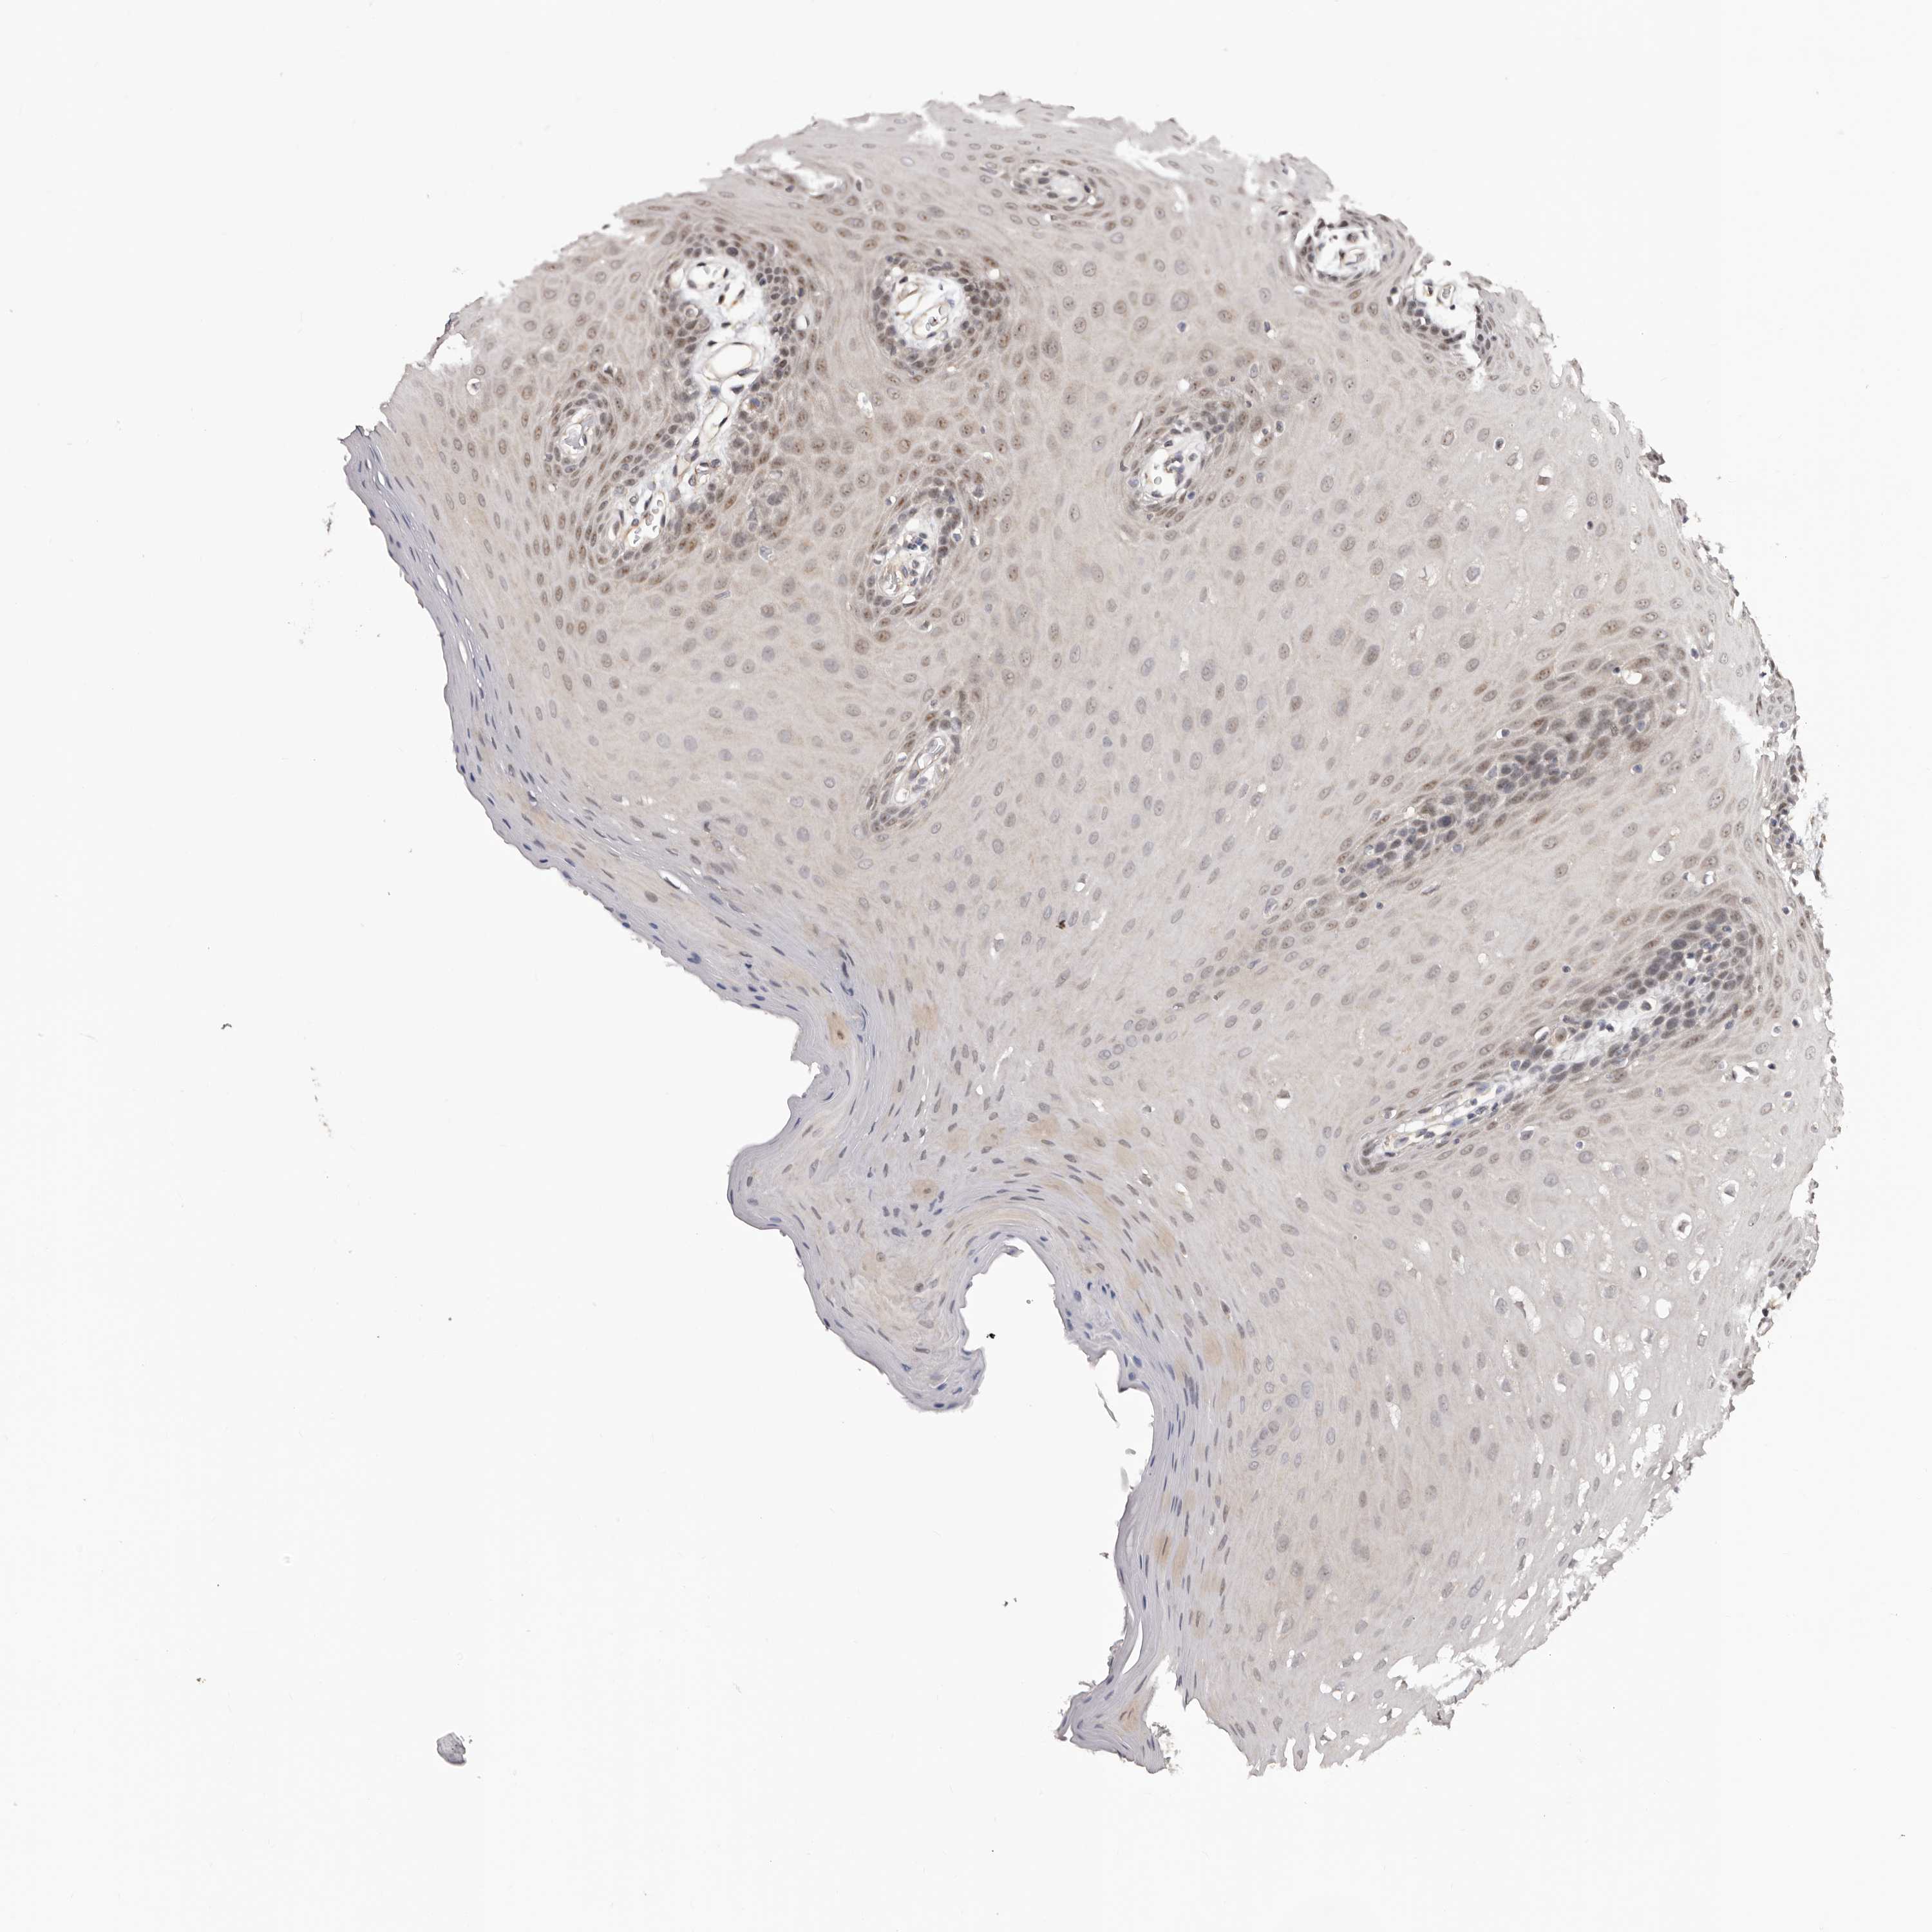

NOL12